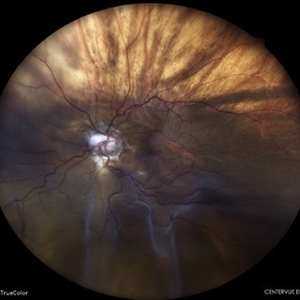

Coats' Disease Montage

Fundus photograph of a 5-year-old male child who presented with unilateral diminution of vision since one month.

Photographer: Dr. Nivesh Gupta, M.S., Retina Foundation, Ahmedabad

Condition/keywords: angiomatosis retinae, Coats' disease, exudative detachment, subretinal exudates